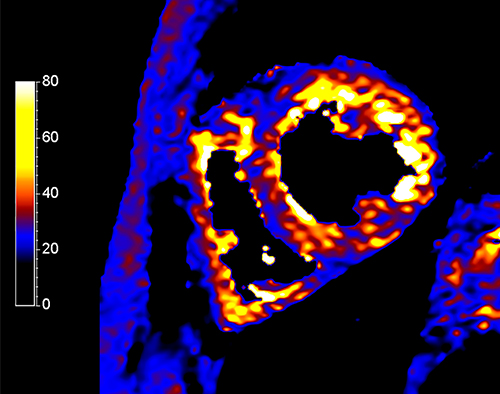

Традиционно для мониторинга степени перегрузки железом используется T2*-картирование, чувствительное к отложениям железа, кальция и пр. Оценивается среднее значение параметра T2* или же анализируются значения в 16 различных сегментах миокарда согласно вышеупомянутой модели. Значения T2*<20 мс указывают на среднюю степень перегрузки, <10 мс - на сильную степень перегрузки железом, которая ассоциируется повышенным риском развития сердечной недостаточности [24]. В связи с этим T2*-картирование занимает важное место в клинической практике для своевременного начала хелаторной терапии.